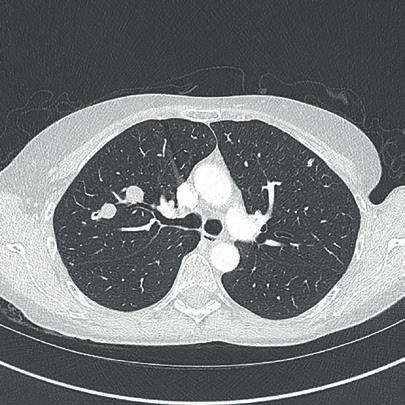

The incidence of lung cancer has increased considerably in the last few decades with the lung as the most common site of metastatic involvement. Despite the improvements in the diagnosis and treatment for malignant lung tumours, the prognosis of the patients is still unsatisfactory.1 Currently, locoregional chemotherapeutic techniques such as transpulmonary chemoembolization (TPCE) for the treatment of lung malignancies have gained increasing importance. The purpose of this retrospective study was to evaluate local tumour response and patient survival after the treatment of pulmonary metastases using TPCE as a palliative treatment method.

In TPCE, a 5 French (Fr) endovascular sheath and 5Fr headhunter catheter are routinely placed transfemorally under fluoroscopy until the pulmonary artery and subsequently the tumourfeeding segmental pulmonary branch are reached. A balloon catheter (up to 7mm in diameter) is optionally placed for better results.2 This selective pulmonary artery catheterisation results in a blockage of the arterial supply to the tumour tissue, resulting in regional ischaemic necrosis in the target tumour tissues while reducing damage to the surrounding normal lung parenchyma. Thereafter, mitomycin

and gemcitabine as chemotherapeutic agents are administered in combination with an embolization of lipiodol and microspheres. This extends the storage time of the injected cytostatics in the tumours and reduces the outflow into

the circulatory system.3 Consequently, the frequency and severity of systemic effects are limited. Other occlusion materials used are coils, polyvinyl alcohol, degradable starch microspheres, and gelatin sponges.

In our study, 223 patients (138 women, 85 men; mean age: 59.3±11.9 years) with unresectable lung metastases and/or not responding to systemic chemotherapy received repetitive TPCE (mean number of sessions 4.7±3.7) between January 1990 and May 2021. Patients had predominant lung metastases and in most cases with bilateral lung involvement. Origin of the metastases were either colorectal carcinoma (n=139) or breast cancer (n=84). Tumour-supplying vessels were catheterised selectively in order to apply chemotherapeutic agents locally, combined with lipiodol and microspheres. The response was assessed according to the revised RECIST criteria.

Of the evaluated 183 cases, partial response was achieved in 4.9% (n=9), stable disease in 62.3% (n=114), and progressive disease in 32.8% (n=60) of the patients. Mean and median overall survival time were 23.5 and 14 months, respectively.

TPCE can be used as a palliative treatment in unresectable lung malignancies to reduce the tumour burden or to achieve local tumour control,4 or as a neoadjuvant or curative treatment option combined with thermal ablation such as radiofrequency ablation (RFA) and microwave ablation (MWA) (Figure 1).5,6

A multicentre study may include a larger population of patients and combine expertise from different institutes. Although TPCE has the potential to improve local tumour control and to prolong survival, randomised controlled trials are still needed.